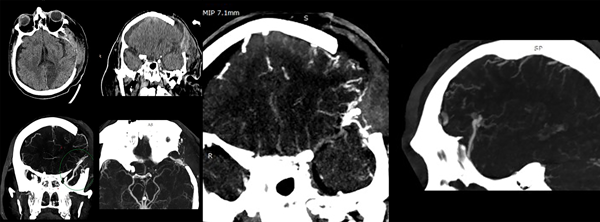

A las 72 horas postoperatorias y con el paciente estable hemodinámicamente, se reconsidera el hallazgo intraoperatorio de los vasos corticales anómalos junto con lo llamativo del volumen del hematoma y se presume un posible sangrado espontáneo. Se decide realizar imagen de control que incluya estudio de los vasos intracraneanos (a tales fines en nuestra institución solo se cuenta con la posibilidad de realizar AngioTC, Fig. 2).

Figura 2. TC y AngioTC a las 72 horas de evacuación del hematoma.

La AngioTC revela craniectomía extensa, retorno a la línea media de estructuras centrales, una nueva área hipodensa que corresponde al territorio vascular de la arteria cerebral posterior izquierda, higroma hemisférico derecho laminar y un hallazgo vascular a nivel del extremo superficial de la cisura silviana, que se observa como un vaso de gran calibre en tiempo venoso del contraste, con un trayecto proximal que termina en contacto con ramas de M3 y un trayecto distal voluminoso que se dirige hacia el polo temporal y se pierde en la base del mismo a nivel del tercio medio de esa misma fosa temporal.

Con los datos obtenidos de este estudio se diagnostica fístula arteriovenosa cerebral, identificando su afluente principal en la cara profunda y superior del trayecto varicoso central, proviniendo aparentemente de ramas de M3 en la profundidad de la cisura silviana. El trayecto varicoso central se extiende sobre la superficie de la cisura homónima y se dirige al polo temporal sin aparente comunicación a los senos durales normales. Se grafican imágenes clave en la Figura 3.